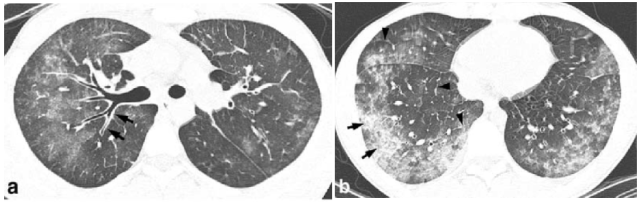

病史:29 岁女性,既往体健。主因「发热 13 天,咳嗽、咳痰 10 天,胸痛 4 天」入院。患者 13 天前无明显诱因出现发热,体温高达 40℃,伴畏寒,3 天后出现咳嗽、咳痰,夜间为甚,伴有解稀水样大便。于当地医院退热、抗炎对症支持治疗,无明显改善;3 天前患者出现左侧胸痛,咳嗽、左侧卧位等动作时疼痛加剧,至我院急诊科查胸部 X 线提示「双肺肺炎」(图 1)。

图 1 胸部 X 线